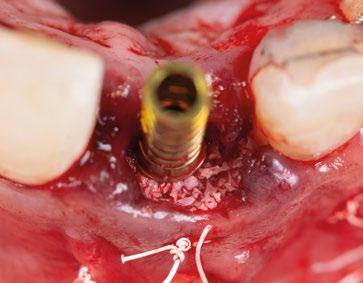

8.- Realizamos osteotomía mediante férula quirúrgica utilizando fresa piloto. (Figuras 22 a 24)

9.- Seguimos preparando el lecho utilizando fresado biológico con la OsseoShaperTM. (Figura 25)

10.- Colocamos implante Nobel Biocare N1TM TiUltra de 3,5x13. (Figura 26)

14.- Rellenamos el gap con creos xenogainTM, compactando para que el hueso llegue lo más apical posible y cubra la superficie implantaria expuesta. (Figura 29)